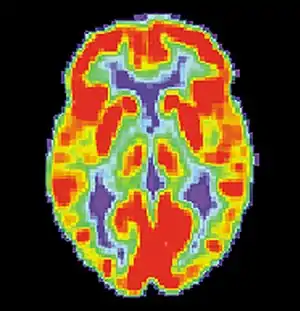

False memories and PET scans

A follow-up to the previous research was conducted by Daniel L. Schacter and colleagues. Similar to the study by Henry L. Roediger and Kathleen McDermott, subjects were read a list of associated words before they went into the PET scanner. During the first scan, subjects would make recognition judgments to determine what were the previous presented words.[2] During the second scan, subjects had to make judgments about words that were not presented. For example: bed, rest, dream, tired, and awake would be in the list but not the word "sleep". As with the study by Henry L. Roediger and Kathleen McDermott, subjects claimed to remember similar amounts of non-presented words as they did the words that were actually presented.[2] The researchers noted that brain activity during the true and false recognition tasks were very similar. Monitoring the blood flow in the brain revealed there were in the left medial temporal lobe for both veridical and illusory recognition.[18]

That is not to say that there were not differences. While monitoring blood flow in the brain during false recognition, a part of the frontal lobe that is thought to be a key monitor of memories actually showed greater activity when presented with a false recognition than with a true one.[2] There seemed to be some discrepancy as subjects attempted to scrutinize the out-placed words, but were overcome by powerful memory illusion.[2] This study demonstrates the ability of technology to help researchers understand to a greater extent the power of false memories.